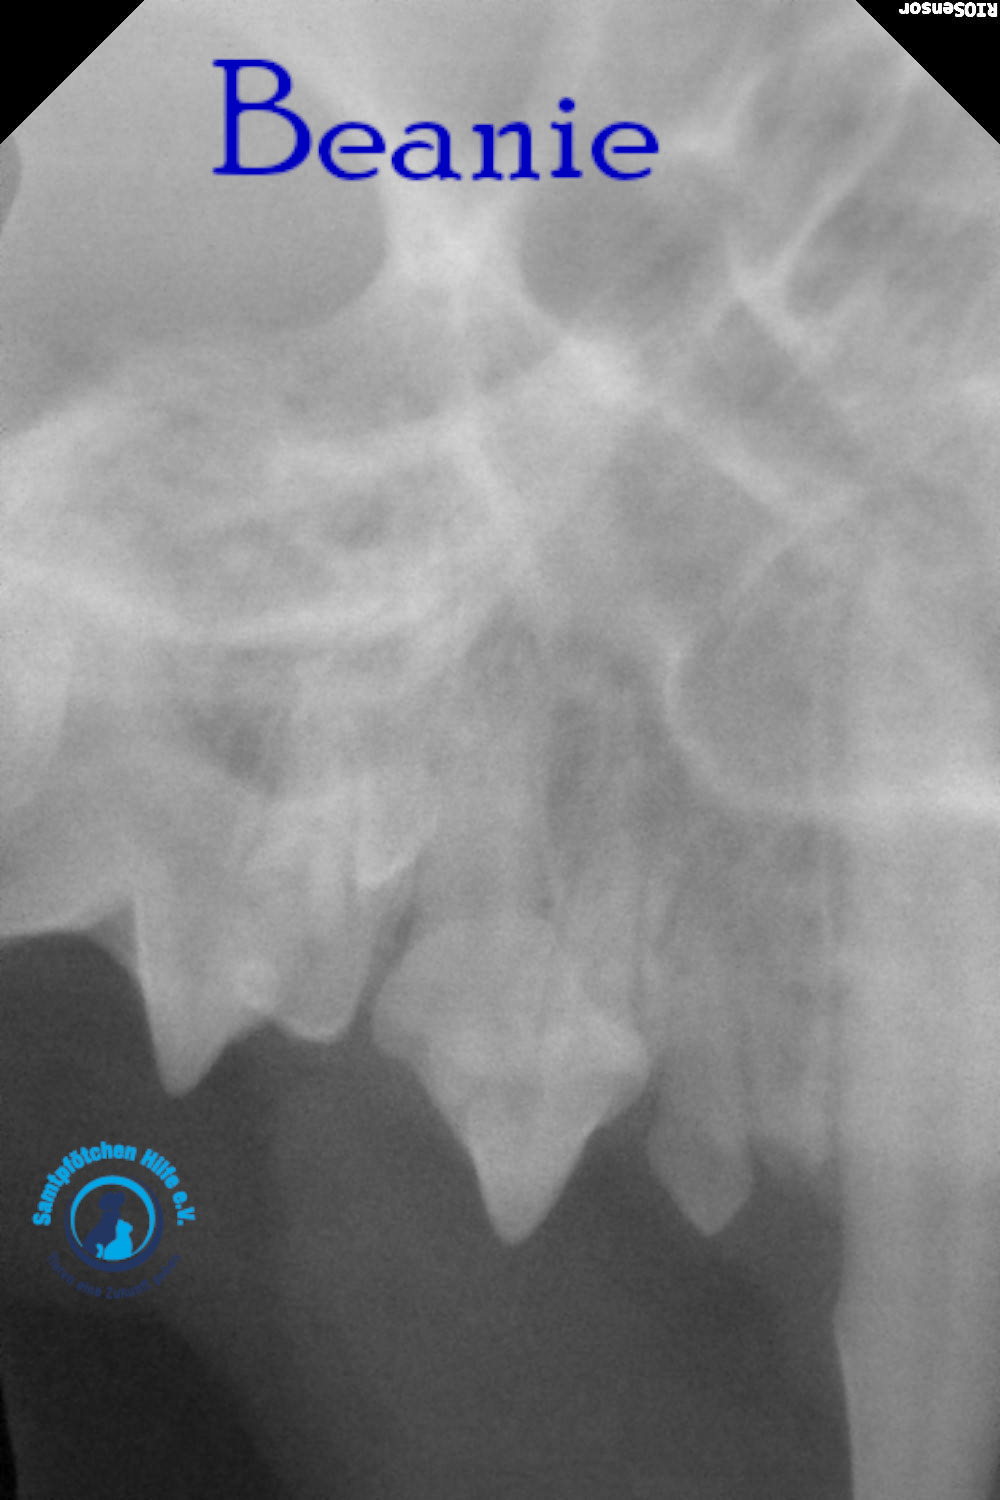

Unsere Beanie hat immer noch Probleme mit der Nasenatmung und musste deshalb zum Tierarzt. Der Arzt nahm Blut für allgemeine Indikatoren und Biochemie sowie PCR für Leukämie und Immunschwäche ab. Auch die Ohren wurden sorgfältig untersucht; Manchmal behindern Polypen in den Ohren die Atmung, aber die Ohren waren sauber. Der Arzt untersuchte auch den Rachenraum. Aufgrund der Untersuchungsergebnisse wurde eine Computertomographie des Gehirns im Bereich der Nase und des Nasenrachens sowie eine tägliche Zahnreinigung verordnet – bei Beanie besteht der Verdacht auf eine juvenile Stomatitis. Wenn Sie jetzt nicht mit der Zahnbehandlung beginnen, müssen in 2-3 Jahren alle Zähne gezogen werden.

Lyudmila schreibt: "Die Ärzte vermuteten, dass etwas in Beanies Nasenrachenraum feststeckte, ein Fremdkörper, der sie am Atmen hinderte. Sie führten eine Operation durch, führten eine Sonde tief ein und spülten sie aus, konnten aber nichts finden. Eine Röntgenaufnahme zeigte leichte Veränderungen in einer Nasennebenhöhle. Außerdem wurde Material aus der Nasenschleimhaut für eine Zytologie entnommen. Das Fazit des Zytologen: Das Material könnte auf einen Polypen in der Nase hinweisen. Da Binis Nasengänge sehr eng sind, ist eine Rhinoskopie möglicherweise nicht möglich. Bisher wurden Hormontropfen in die Nase empfohlen, die aber kaum helfen. Eine Konsultation mit einem Chirurgen, der Rhinoskopie durchführt, ist erforderlich; unsere Tierklinik führt diese Untersuchung nicht durch.